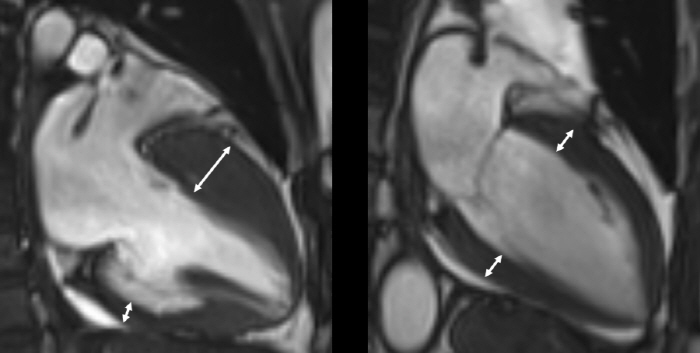

진단은 심장초음파, 자기공명영상 등 영상검사를 통해 이뤄지며, 비후된 심근 내에 섬유화가 진행돼 있거나, 근육조직이 지방조직으로 변성이 돼 있는 상태가 관찰된다. 하지만 이 같은 조직변성이 없는 비후성 심근병증도 있는 만큼 전문의의 종합적 판단이 중요하다.